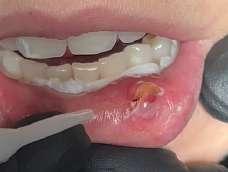

Il mucocele del cavo orale è la seconda lesione più comune. Nella fascia di età compresa tra 10 e 29 anni, il tasso di incidenza è più elevato. Il mucocele è caratterizzato da un accumulo di mucine. Ha una forma a cupola. Di solito hanno un colore bluastro. Il

mucocele si trova più comunemente sul labbro inferiore, seguito dalla mucosa buccale e dal pavimento della bocca. L'incisione tradizionale con bisturi e/o l'escissione chirurgica, la marsupializzazione, la micromarsupializzazione, l'iniezione di corticosteroidi, l'agente sclerosante, la criochirurgia, l'elettrochirurgia e il laser sono tutte procedure validate per il trattamento del mucocele in letteratura.

I laser a diodi forniscono una guarigione delle ferite e un tasso di recupero più rapidi rispetto ai loro rivali. Grazie alle sue

qualità antibatteriche e antinfiammatorie, questa terapia laser ha l'ulteriore vantaggio di migliorare la guarigione delle ferite senza infezioni o edema.

Le procedure laser-assistite sui tessuti molli presentano i vantaggi di un minimo sanguinamento intraoperatorio, edema e dolore postoperatorio, oltre a tempi chirurgici, cicatrici e coagulazione minimi.

La dimensione di un sito chirurgico determina se vengono utilizzate o meno le suture. Le procedure che comportano un'escissione piccola o significativa dei tessuti molli, l'esposizione dell'impianto con o senza taglio osseo, possono essere eseguite in pazienti con problemi di sanguinamento.

Questo caso è coerente con precedenti segnalazioni di escissione del mucocele utilizzando un laser a diodi.

L'enorme quantità di tessuto rimosso e il livello di comfort del paziente supportano ulteriormente il fatto innovativo che può essere utilizzato anche per il mucocele di grandi dimensioni.

I mucoceli della mucosa orale sono malattie tumorali benigne delle ghiandole salivari minori della mucosa orale. Si verificano più comunemente nella mucosa labiale. Possono essere causate da una rottura dell'epitelio della ghiandola che secerne saliva nello spazio extraghiandolare e forma una pseudocisti (mucoceli da stravaso) oppure da un blocco del flusso salivare dovuto ad una proliferazione epiteliale del dotto escretore che forma una cisti salivare (cisti da ritenzione).